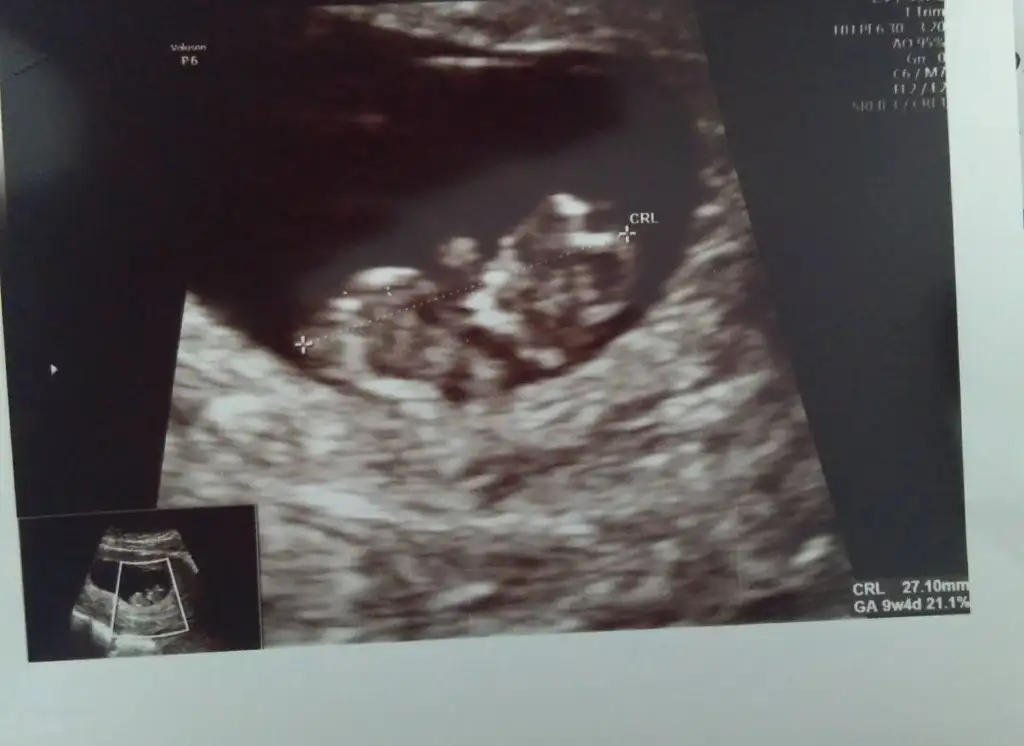

Kızlar bugün dr.kontrolum vardı ilk defa eli ayağı hareket halinde gördüm ense kalınlığı iyi dedi ikili üçlü testten bahsetti yasin var o yüzden risk çıkar ama kesin sonuç olmaz dedi riskli çıkarsa bebeği aldirirmisin deyince yok asla dedim o halde o testlere gerek yok sadece 20 haftada ayrıntılı ultrason yaparız dedi d vitamini demir ilacı verdi

11-12 civarı varsa onu da nuba göre yorumlarız atın kızlar

Su an 10+5 12.hafta civarı gidecem bakalım bi ağzın bal yesin

+ nın üstünde bi çizgi var canım dikkat ettiysen o nub oluyor. Yukarı doğru seninki büyük ihtimal erkek